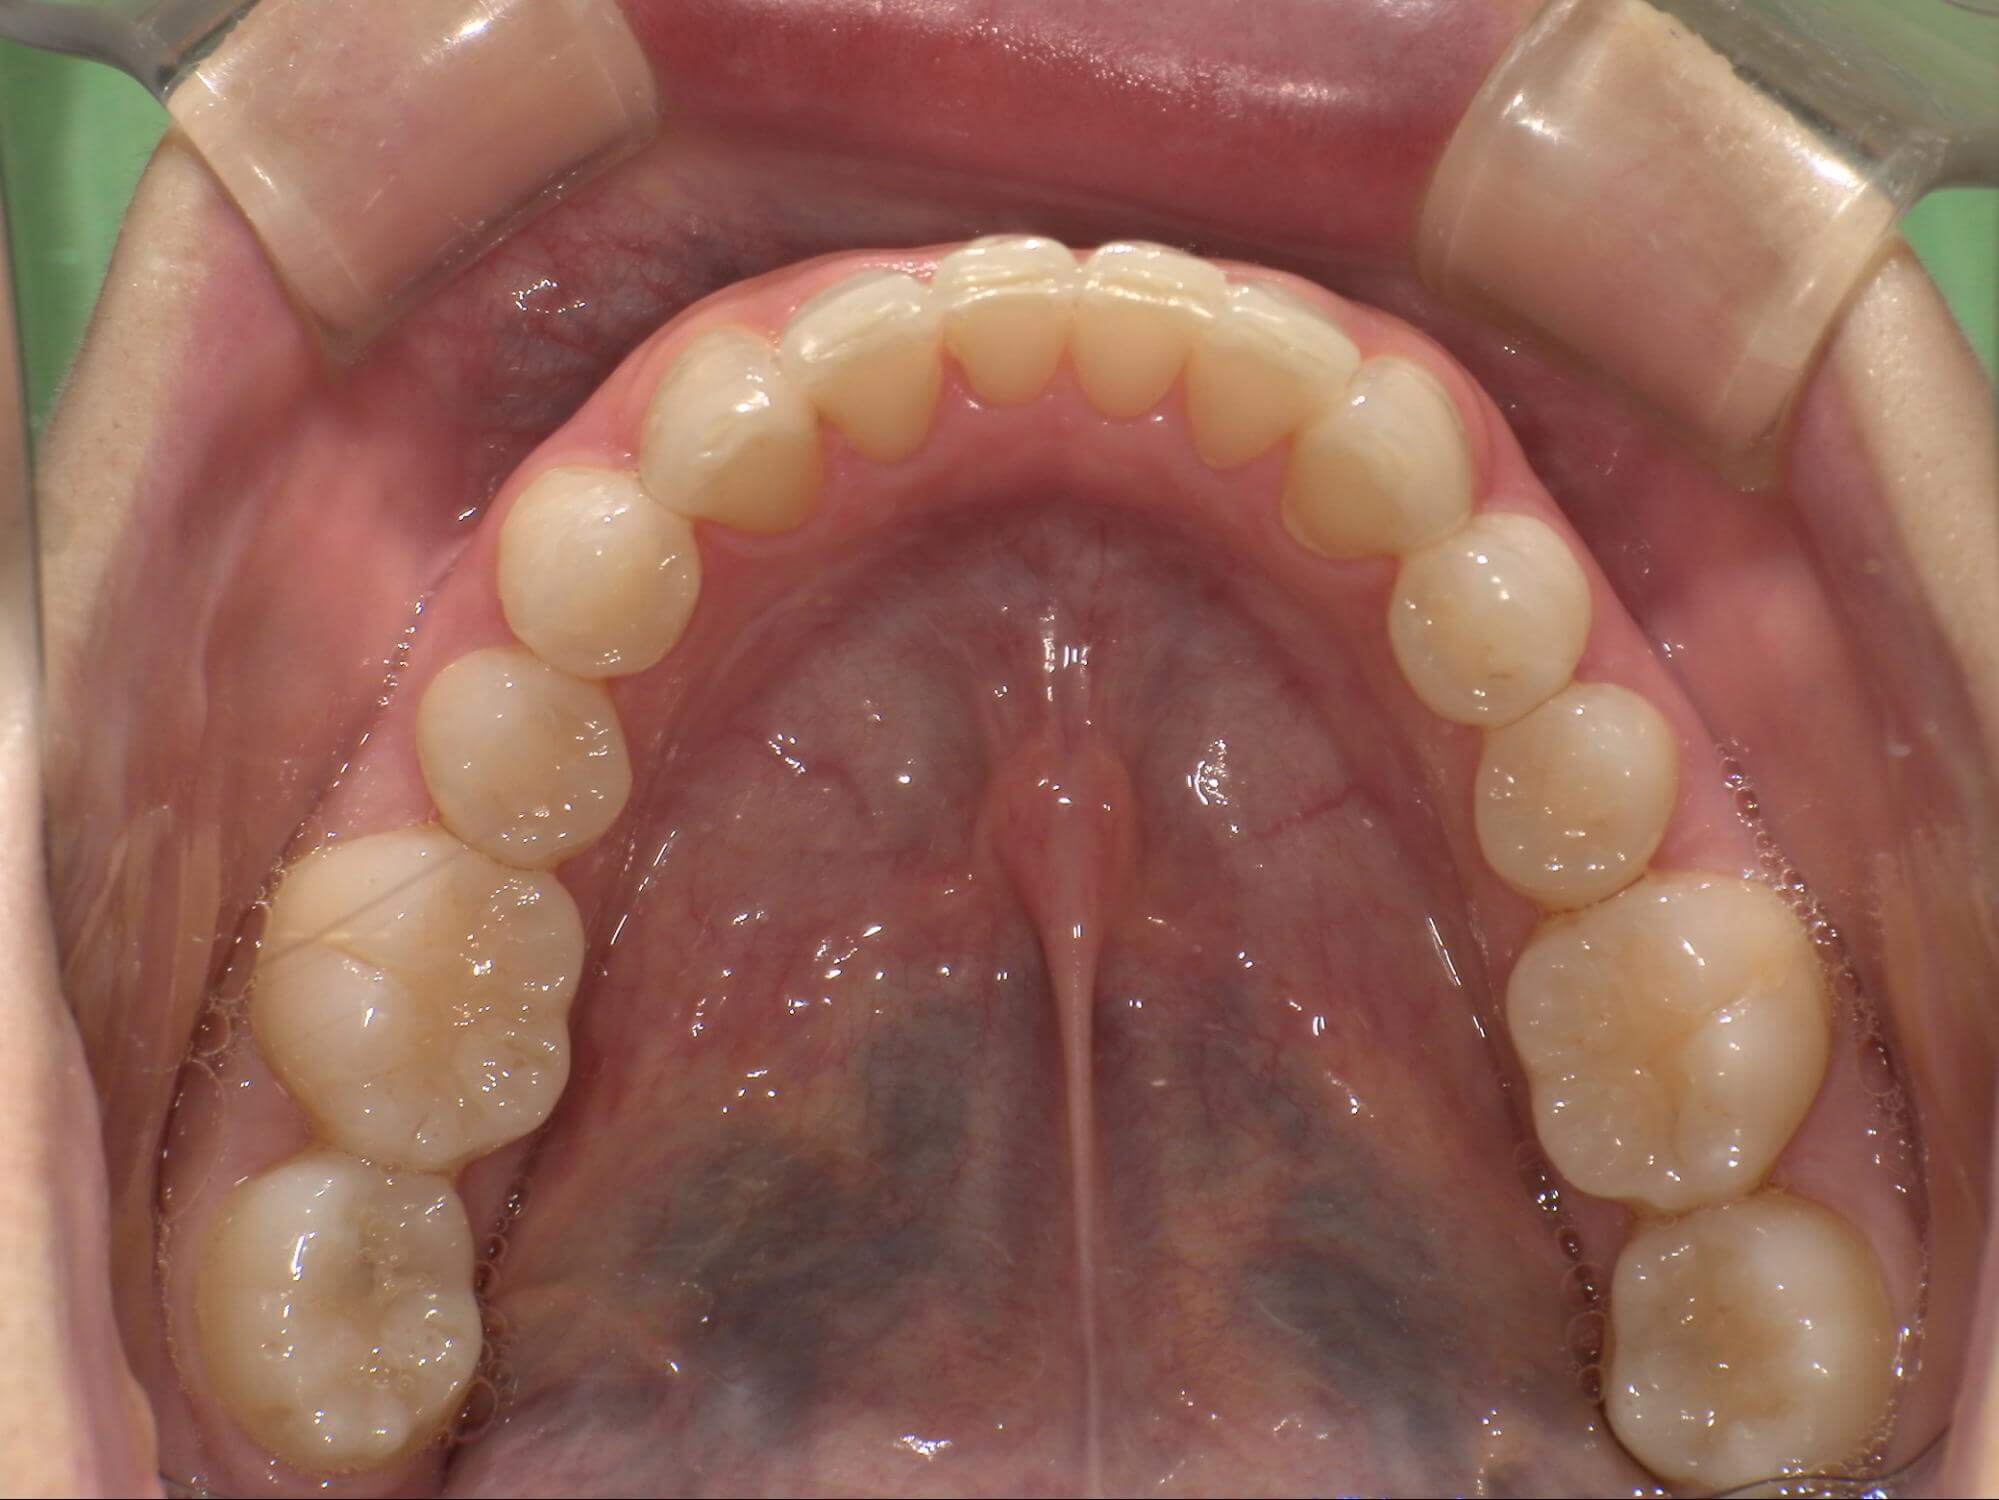

| 年齢・性別 | – |

|---|---|

| 主訴 | 叢生が気になる |

| 治療期間・回数 | 1年9ヶ月 |

| 費用 | 1,011,000円 |